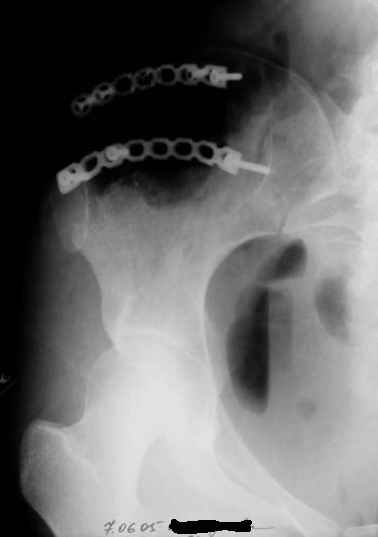

Уважаемые коллеги, больную прооперировали. После выделения остеохондрома резецирована в пределах неизменённой кости. Выявлено, что гребень подвздошой кости не пострадал от опухоли. В результате резекции сформирован сквозной дефект в крыле подвздошной кости треугольной формы 6х7х8 см. В качестве трансплантата использована наружная кортикальная пластинка заднего отдела крыла подвздошной кости.

Трансплантат фиксирован на месте дефекта при помощи шурупов и проволоки. Кровопотеря 550 мл.

На фото этапы операции, R-gr.